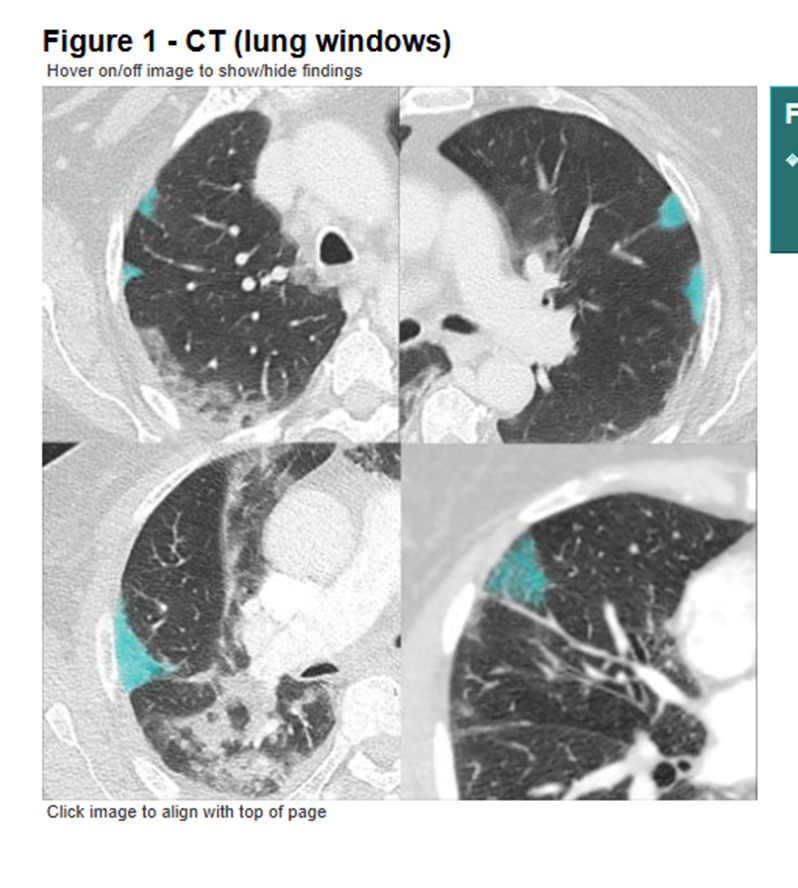

The early papers from China showed distinct patterns of lung damage on CT scans which helped to make the diagnosis, but this was not the main question I had.

The areas of lung damage looked like what we see when someone has blood clots in the lungs.

5/25 bit.ly/4j6fIpxImage

The pattern of lung disease we saw on medical imaging in people with #COVID-19 tells us that the disease is NOT pneumonia, it is a vasculopathy (disease of blood vessels).